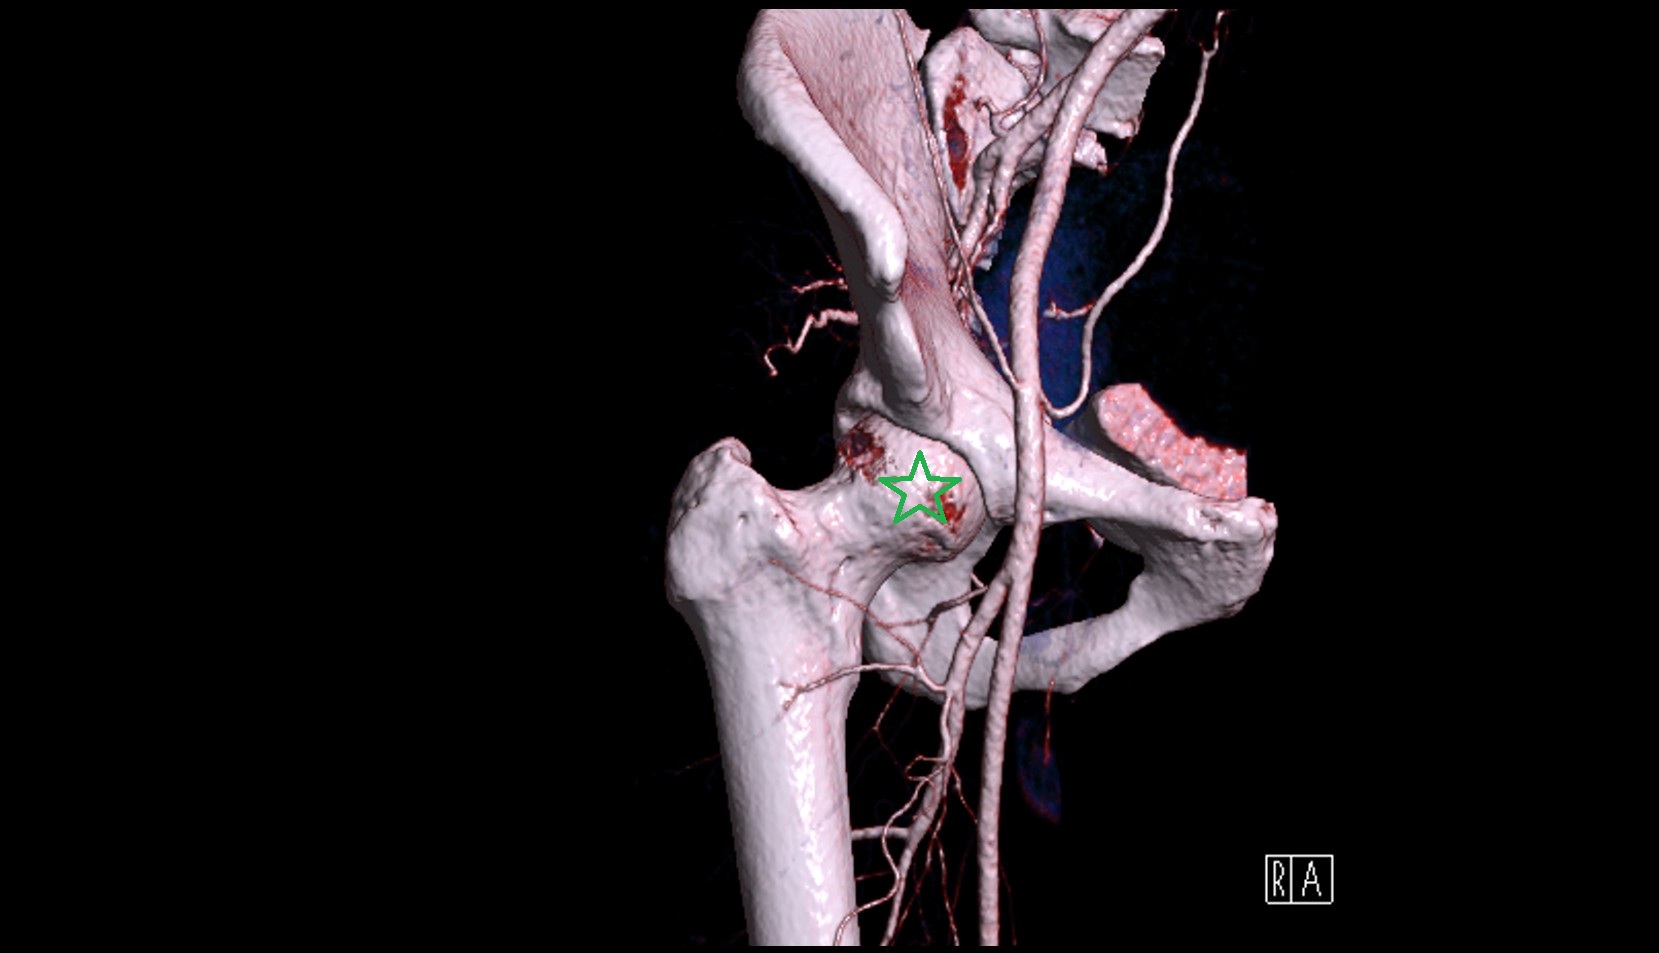

- Lateral circumflex femoral artery

- Deep femoral artery (profunda femoris)

- Femoral artery

- Medial circumflex femoral artery